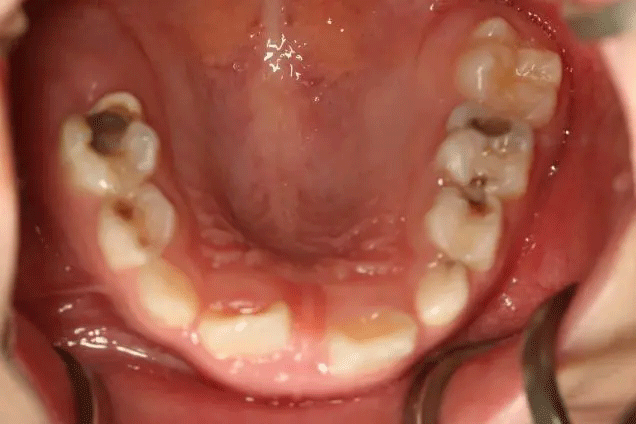

在門診中發(fā)現(xiàn)

來口腔科檢查的孩子

有些牙齒都已經(jīng)爛得很嚴重了

甚至牙齒幾乎都爛光僅剩下牙根